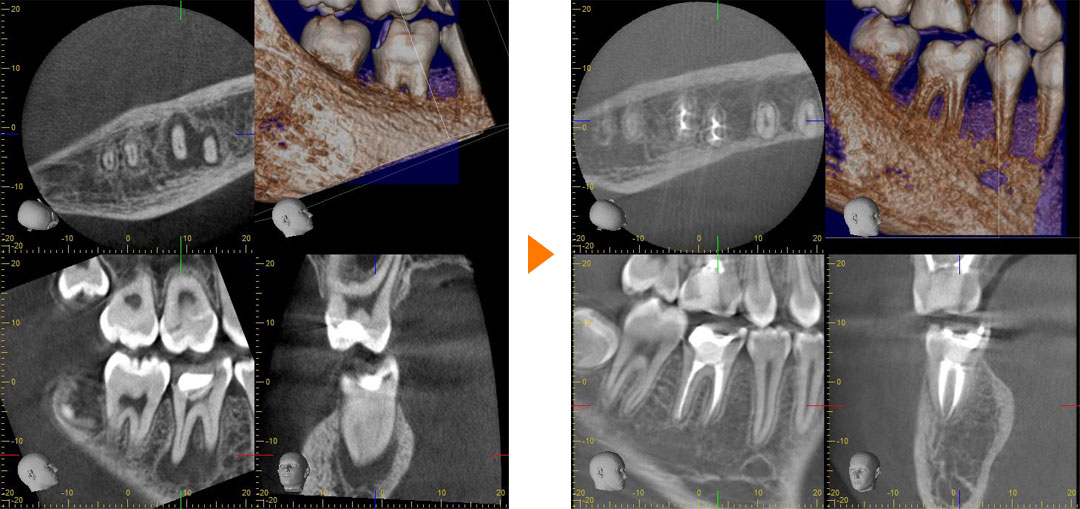

右下の奥歯が痛いとのことで来院された患者さん。

CTにて2次う蝕、根尖病変、根管が4本あることを確認し精密根管治療を行いました。

1年後のCTで病変が治癒していることが確認できます。